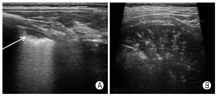

肺点:随着呼吸运动,在实时超声下所见肺滑动存在与肺滑动消失交替点出现的分界点称为肺点(图8A所示)。

肺搏动征:胸膜线与心脏一致的运动,反映肺充气不足,该征象的存在可排除气胸。

平流层征:当肺滑动消失时,在M型超声下,胸膜线下方的颗粒样点状回声被一系列平行线所替代,称平流层征或条形码征(图8B)。

气胸:存在胸膜线与A线,肺滑动征消失,无B线存在,可见肺点,M型表现为平流层征,其诊断流程如图11所示。